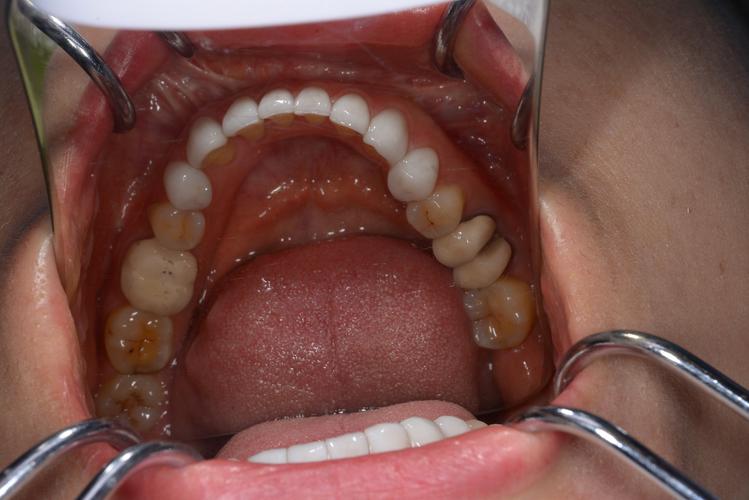

(图片来源网络,侵删)- 优势: 另一家实力雄厚的三甲综合医院,口腔科种植技术成熟,尤其在数字化种植和即刻修复方面有较多实践,医生团队经验丰富。